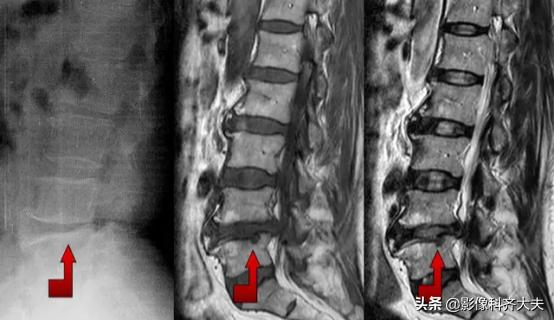

Schmorl结节(许莫氏结节)

Schmorl结节(许莫氏结节),是椎间盘退变时,软骨板变薄及玻璃样变,甚至消失。髓核经软骨板的薄弱或者缺损部疝入椎体内,在椎体内形成软骨结节。

是髓核于椎体上面或者下面形成的圆形或者半圆形的骨质凹陷区,其边缘有硬化。可对称见于相邻两个椎体的上下面,并且可以累及多个椎体。

可以说算是一种特殊类型的椎间盘突出。只不过不像普通椎间盘突出是突出于椎体后缘,而是突出到上下椎体里!

在影像上看,椎体上下缘弧形的凹陷或者骨性透亮区,伴有不同程度的边缘硬化,广泛硬化时椎体呈象牙质样。